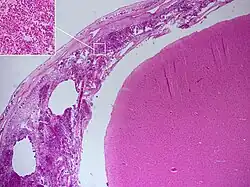

![]() Zdjęcie mikroskopowe bakteryjnego zapalenia opon mózgowych. | |

Patologia

Zapalenie obejmuje tkanki opon, a często przylegające do nich części mózgowia i rdzenia.